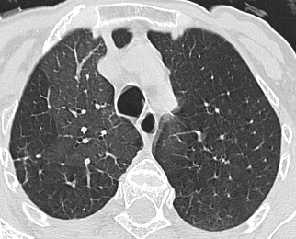

CT/HRCT

• Directly visualize clot in central pulmonary artery

• CT angiograms highly sensitive and specific

• Mosaic perfusion, usually less well defined than pattern with small airways disease

• Due to vascular obstruction with areas of hypoperfusion and overperfusion

• No air trapping with expiratory scanning